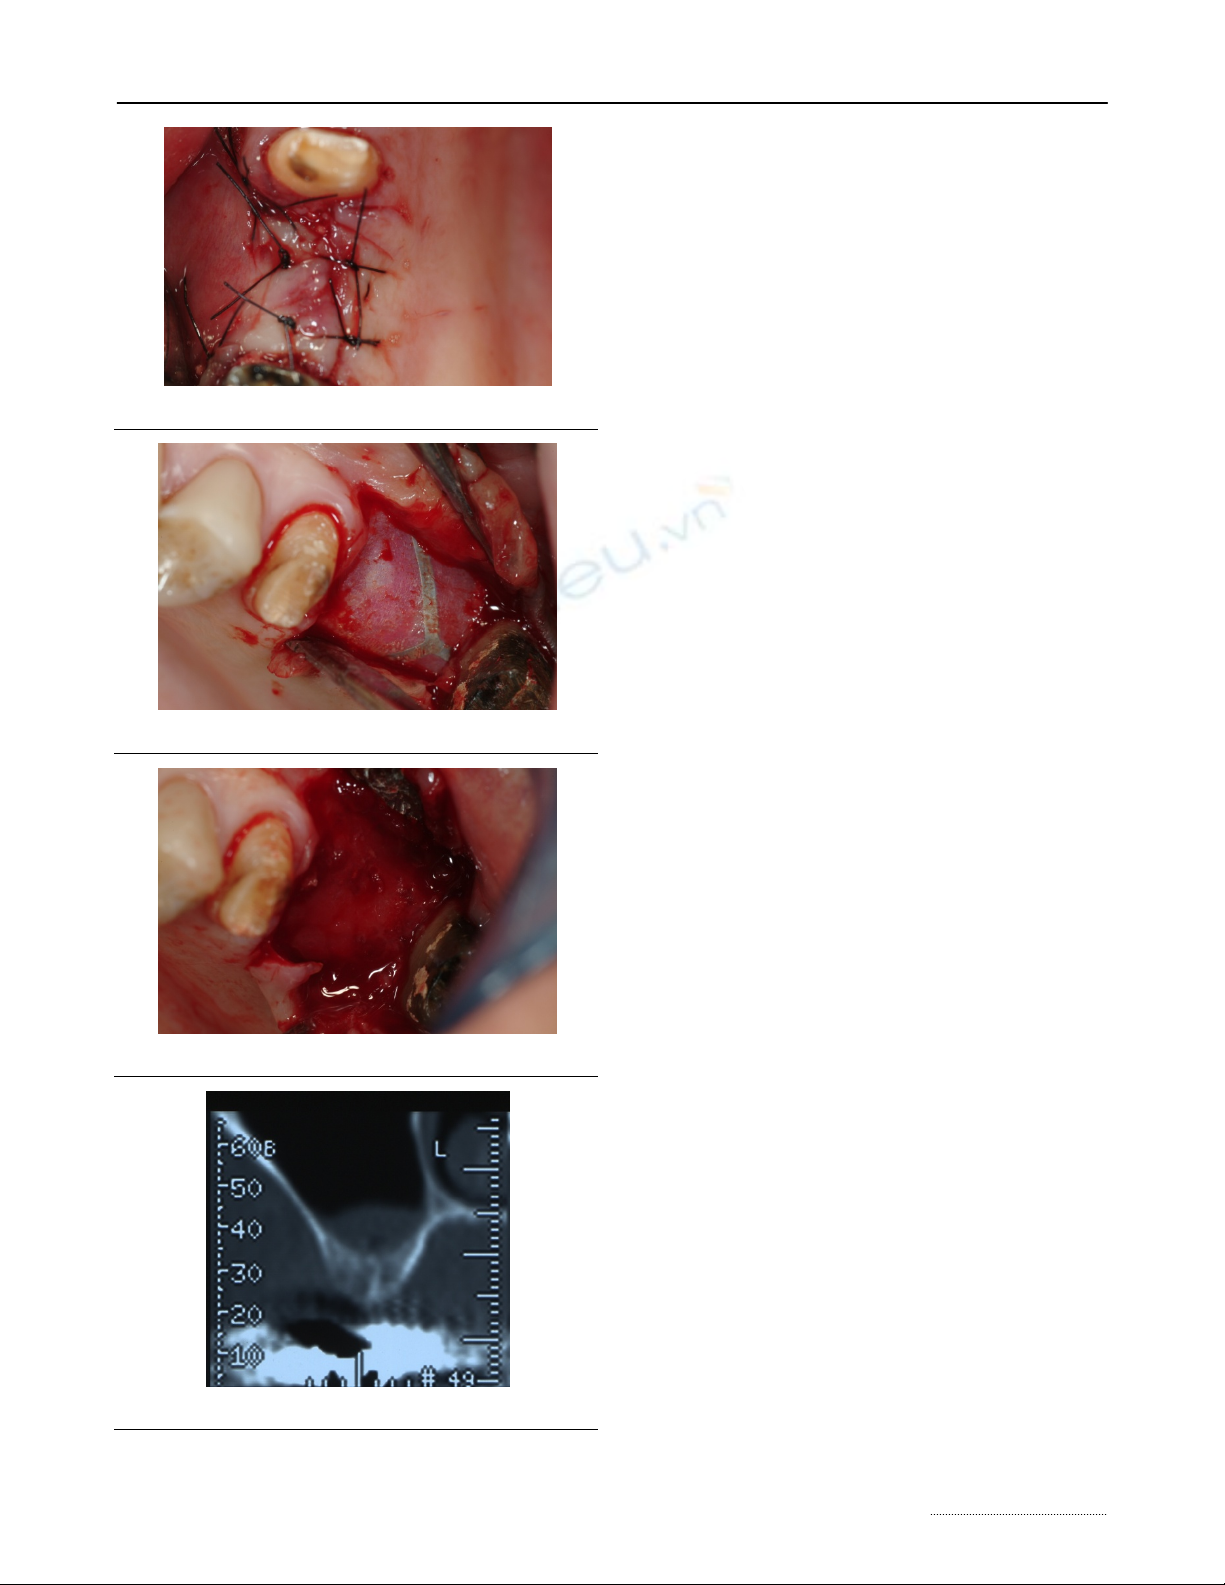

A 3.0 silk detached suture was performed (Fig.8)

and topic medication with povidone-iodine solution

was applied. A systemic antibiotic prophylaxis with

amoxicilline and clavulanic acid 1g was prescribed

after 6 hours from surgery.

At 10 days from surgery the suture was removed

and the mucosa appeared healthy.

At 45 days from surgery, after non-reabsorbable

membrane removal (Fig. 9), the clinical control

showed an uneventful healing process with complete

Int. J. Med. Sci. 2010, 7

http://www.medsci.org

269

elimination of the bone defect. (Fig. 10). No pain, fever

or discomforts were described. The soft tissues ap-

peared healthy, with normal color, consistence and no

bleeding was present in the incision site and around

the periodontal pockets of mesial and distal teeth.

The 6 months control showed a normal healing

process. The radiographic evaluation with Compute-

rized Tomography demonstrated a complete regene-

ration of the osseous sinus floor (Fig.11).

Figure 8. Sutured flap.

Figure 9. Non-reabsorbable membrane removal.

Figure 10. Clinical evidence of bone healing.

Figure 11. CT at 6 months.